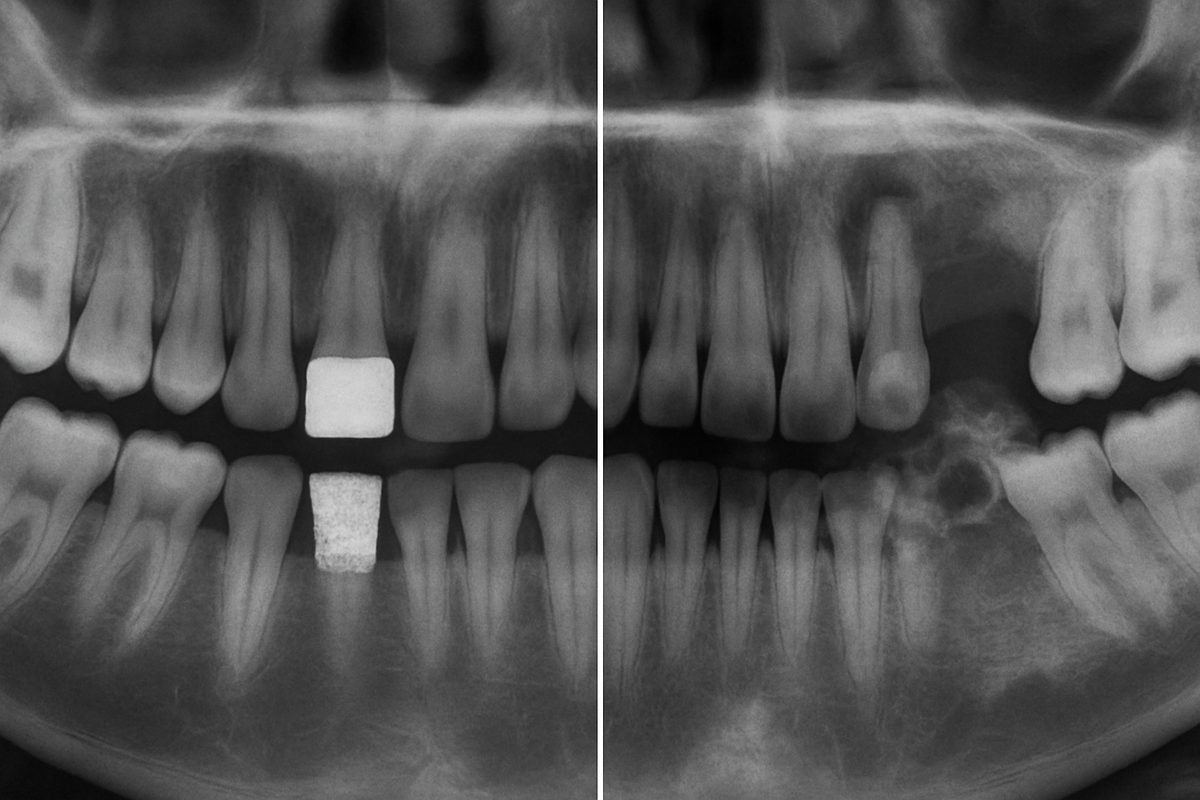

Intro: A dental bone graft is a procedure that adds bone to the jaw so a dental implant can be placed securely. Grafts restore lost bone after tooth loss, infection, or injury. This post covers the common complications of dental bone graft in Radcliff, KY, how to spot problems, when to act, and simple steps you can take to lower your risk.

A bone graft uses bone material to rebuild areas of the jaw that are too thin or weak for an implant. Types include autograft (your own bone), allograft (donor bone), xenograft (animal bone), and synthetic bone substitutes. Grafts give the jaw a stable base so a titanium implant post can integrate and support a crown or denture. This helps address lost bone and provides a strong foundation.